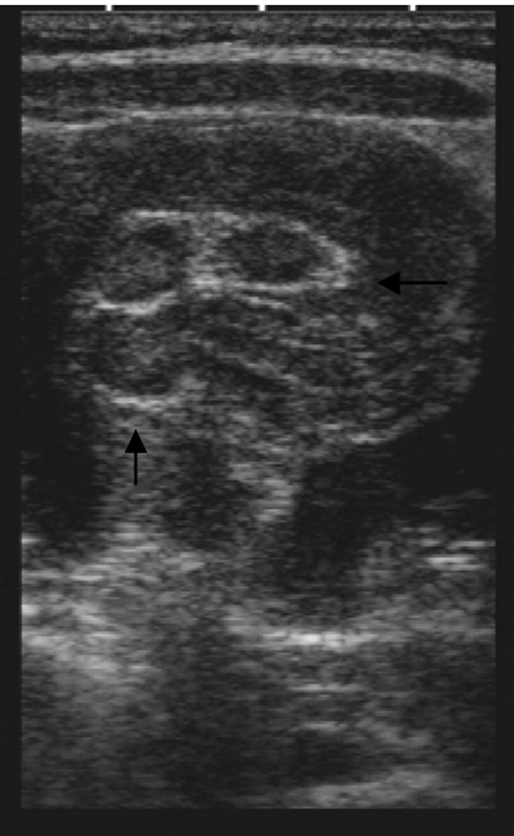

Figure 1. Intussusception “pseudokidney sign” described on pediatric patient in 2009

None of this has prevented the development of more distinct adaptations of POCUS for the pediatric population. Unique applications in children have included infant lumbar punctures guided by direct visualization of the cauda equina, protocols for intussusception, algorithms to confirm endotracheal tube placement, and the expansion of ultrasound first approach to appendicitis among many more yet at bedside. Bedside experience coupled with research has uncovered unique advantages our smaller patients offer in regard to image depth and clarity for structures not well imaged in adults. As a result, what has followed includes specific probe advancements allowing access to higher frequency and smaller footprints. This has allowed visualization of submillimeter neonatal vasculature and the ability to peer between infant ribs and tailor neonatal presets.

- Kairam N, Kaiafis C, Shih R. Diagnosis of pediatric intussusception by an emergency physician-performed bedside ultrasound: a case report. Pediatr Emerg Care. 2009;25(3):77-180.